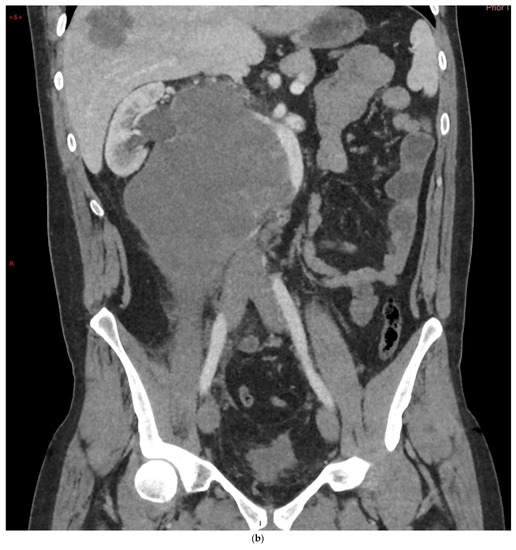

4.1. Seminomatous Germ Cell Tumour

| Seminomas | Homogenous and hypoechoic Well circumscribed Occasionally contain cystic components or calcifications |